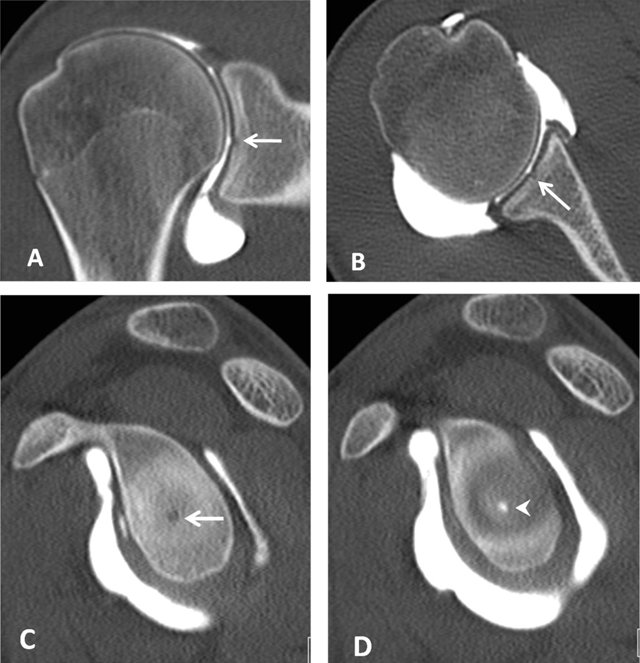

Figure 7

Bare area of the glenoid on CTA. (A) Coronal, (B) Axial and (C, D) Sagittal reconstructed CTA images demonstrate in the mid third of the glenoid a defect of the hyaline cartilage located centrally (arrows, A–C). On D, the defect is filled up by the injected contrast (arrowhead).